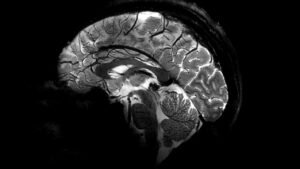

Vücudumuzun tüm kontrolü omurga üzerinden beyne bağlanan sinir hücreleri aracılığıyla gerçekleştirilir. Travmalarda felç oluşumuna sebebiyet veren, bu sinirlerin hasar görmesi ve beyinle uzuvların arasındaki elektrik bağlantısının kopmasıdır. Bugüne kadar geliştirilen teknoloji destekli çözümlerden biri bu bağlantının tekrar sağlanması için yapay elektrik devrelerinin kullanılmasıydı. Şimdi araştırmacılar bu tedaviyi dört hasta üzerinde başarıyla denediklerini ve iki seneyi aşkın süredir felçli olan dört hastaya hareket yeteneğini bir ölçüde geri kazandırdıklarını belirtiyor.